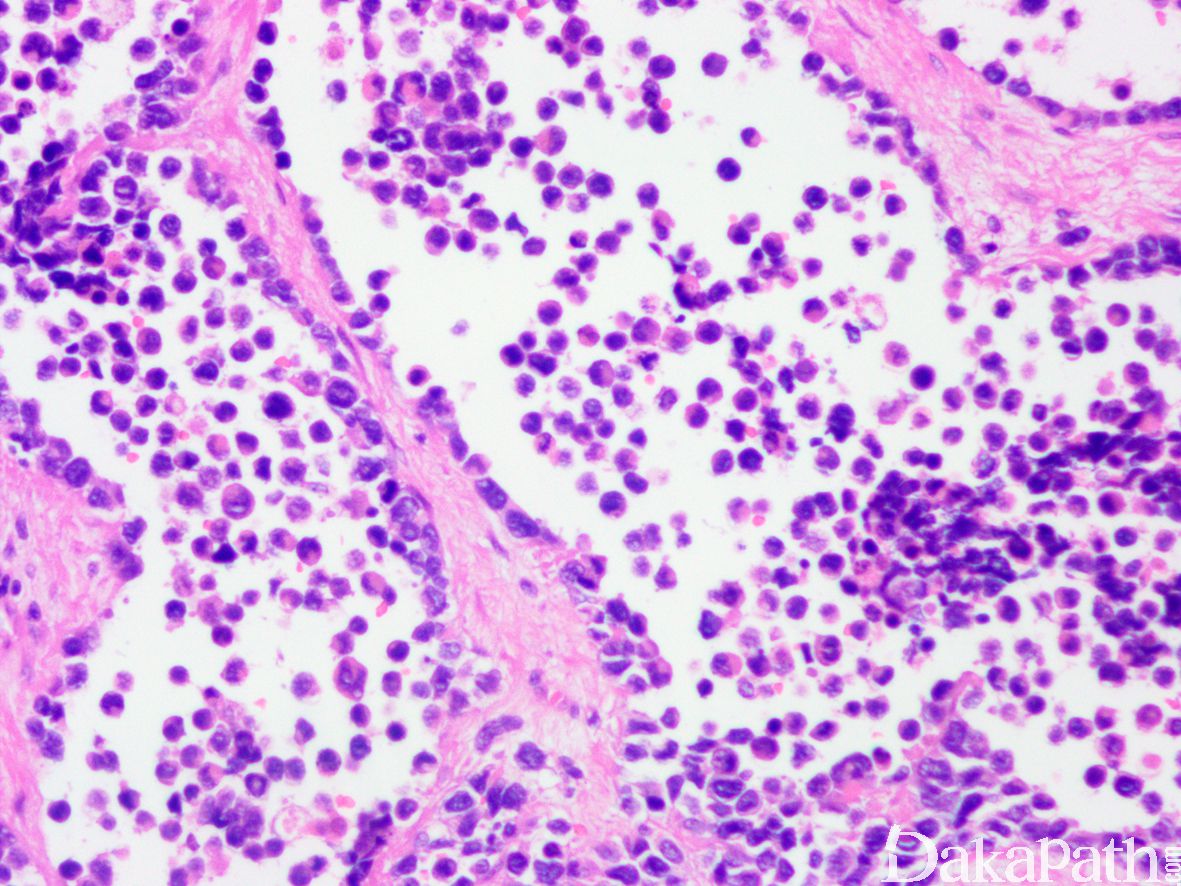

9. 实体型:

10. 由实性的瘤细胞巢组成,瘤细胞圆而较一致,具有纤细的空泡状染色质和小的核仁,部分病例瘤细胞胞质丰富而淡染或透明,类似肾透明细胞癌或软组织透明细胞肉瘤,称透明细胞变型;;

11. 仅偶见或无明显的假腺泡状结构。